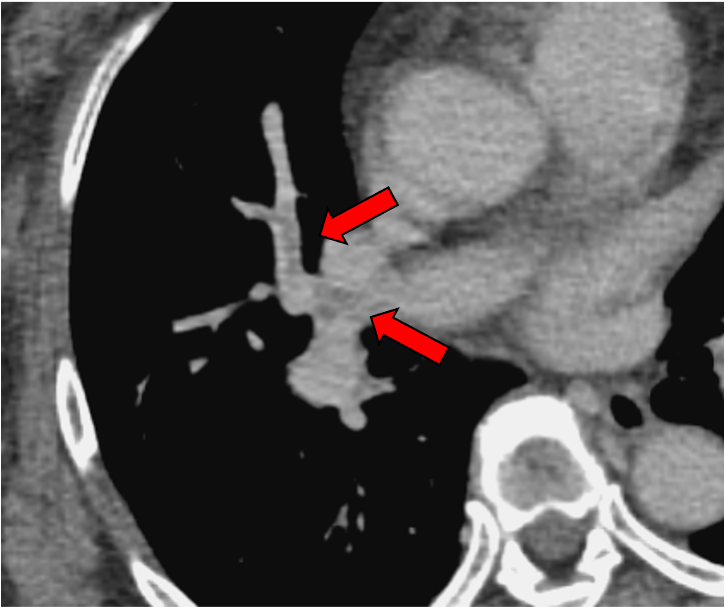

乳癌化学療法の治療効果判定CTに映り込んでいた偶発肺塞栓。通常の門脈相120kVp画像では肺動脈の造影効果が乏しく、血栓を見逃してしまうリスクがある。これに対して、Dual-energy CTの仮想単色X線エネルギー画像(MonoE 40keV)では肺動脈のヨードコントラストが劇的に向上しており、造影欠損を示す肺塞栓を高い確信度で診断可能である。本症例では肺動脈プロトコルでの再撮影を行うことなく、速やかに抗凝固療法が開始され、その後、血栓の消失が確認された。

担癌患者は、腫瘍に伴う凝固能亢進に加えて、臥床、手術、中心静脈カテーテル留置、薬剤、感染症といったがん治療中に生じうる様々な要因により、肺塞栓症を生じるリスクが高い。肺塞栓症に対する画像診断のゴールドスタンダードは造影CTである。肺動脈相の撮影により非侵襲的かつ正確に血栓を検出することが可能であるが、すべての担癌患者に肺動脈相撮影を追加するのは現実的ではない。その一方で、ルーチンに実施される門脈相CTでは、肺動脈の造影効果が不十分のため、偶発的な肺塞栓症を見逃してしまうリスクがあるというジレンマが存在する。

CT技術や撮像プロトコル設定について